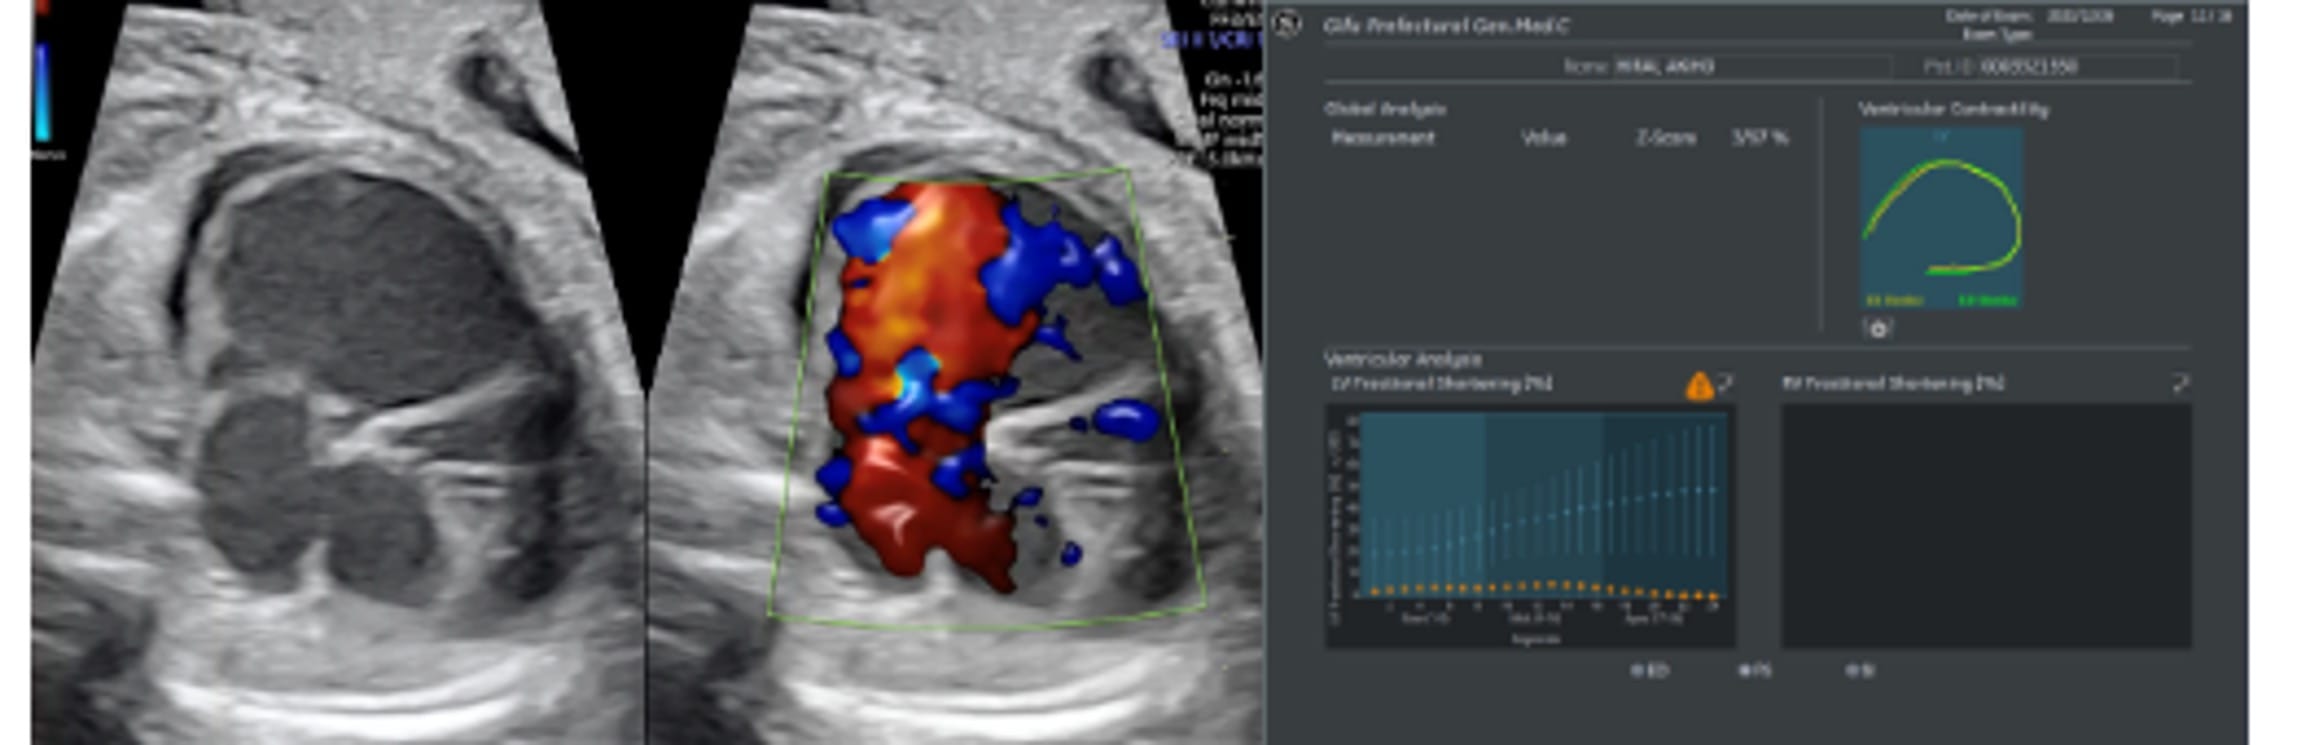

Fetal HQ

Fetal HQ®はSpeckle-Tracking法を用いて胎児心室壁の運動を解析する方法です。Speckle-Tracking法とは心筋の断層エコー画像上の小斑点(speckle)を追跡し心筋局所の機能を解析する方法で、成人の心臓超音波検査でも用いられています。一回数秒の動画の保存で複数の心機能が同時に評価できる新しい検査法です。

Fetal HQで測定できる項目

Fractional shortning

(拡張末期径−収縮末期径)/拡張末期径×100で表され、短軸で収縮能を評価する。SegmentごとにFSを算出できる。

Fractional area change

(拡張末期面積–収縮末期面積)/拡張末期面積×100で表され、面積で収縮能を評価する。

Global strain

(収縮末期心室内周長−拡張末期心室内周長)/拡張末期心室内周長×100で表され、心筋全体のストレイン(伸び縮み)を数値化することで心筋の三次元的な動きを評価する。

Fetal HQの臨床における活用はまだ限定的です。当院では先天性心疾患の胎児や、双胎間輸血症候群・胎児胸水・胎児貧血といった胎児治療が必要な胎児の心機能を評価するために、従来用いられている心機能の評価項目に加え、Fetal HQを用いて心エコー検査を行っています。データを積み上げ、Fetal HQの活用の幅を広げていきます。

胎児心不全の一例:著明な心拡大と収縮機能低下を認める